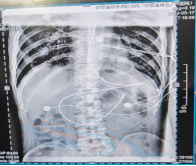

图为术后两名患者的床旁腹部平片检查结果,显示位置良好